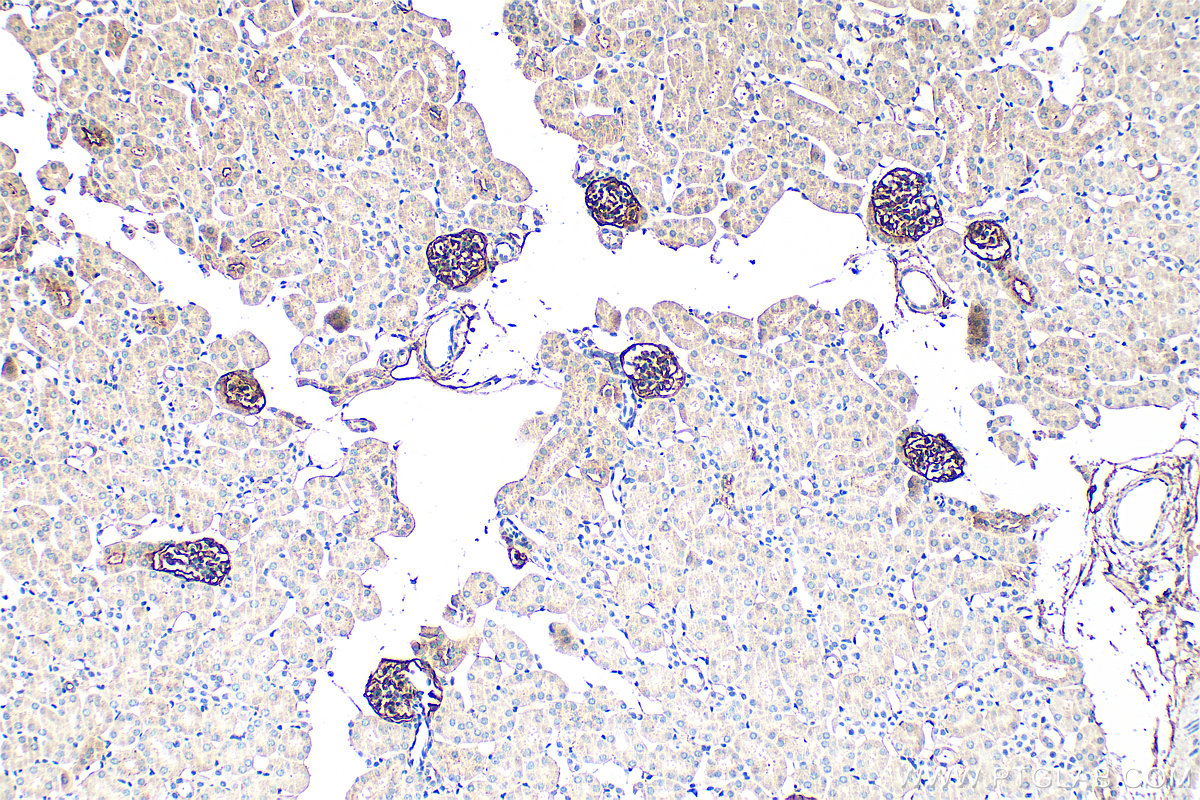

| Positive IHC detected in | mouse lung tissue, mouse kidney tissue Note: suggested antigen retrieval with TE buffer pH 9.0; (*) Alternatively, antigen retrieval may be performed with citrate buffer pH 6.0 |

| Immunohistochemistry (IHC) | IHC : 1:400-1:1600 |

33099-1-AP targets Podoplanin in WB, IHC, ELISA applications and shows reactivity with mouse samples.

Podoplanin was identified as a glycoprotein found in the cell membranes of glomerular epithelial cells (podocyte) (PMID: 9327748). It is a lymphatic marker because the expression of podoplanin has been detected in lymphatic but not blood vascular endothelium, and is useful as the marker of tumor-associated Lymphangiogenesis. Podoplanin has a function in developing testis, most likely at the level of cell-cell interactions among pre-meiotic germ cells and immature Sertoli cells. It may be involved in cell migration and/or actin cytoskeleton organization. When expressed in keratinocytes, PDPN induces changes in cell morphology with transfected cells showing an elongated shape, numerous membrane protrusions, major reorganization of the actin cytoskeleton, increased motility and decreased cell adhesion. It is required for normal lung cell proliferation and alveolus formation at birth. PDPN induces platelet aggregation. It does not have any effect on folic acid or amino acid transport and does not function as a water channel or as a regulator of aquaporin-type water channels.